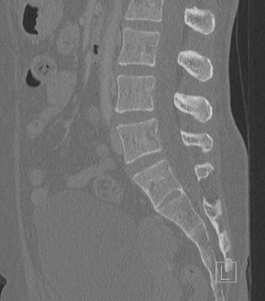

- Compter depuis T12 (qui a une petite cote flottante)

- T12 a des apophyses très verticales et pas vraiment de transverse alors que L1 sont plus horizontales et elle a des transverses

T12 (a) avec sa cote, L1 (b) avec ses processus transverses

Sacralisation de L5

- La plus fréquente (17% de la population)

- 4 vertèbres lombaires sans cote

- Wedging de la vertèbre lombaire transitonelle

- Absence ou hypoplasie de disque intervertébral ou d’articulations facettaires

Lombalisation de S1

- Moins fréquente

- 6 vertebres lombaires sans cote

- Aspect carré de la vertèbres sacrale lombalisée

- Disque intervertébral S1/S2 et articulations facettaires

Classification de Castellvi

anomalie de transition